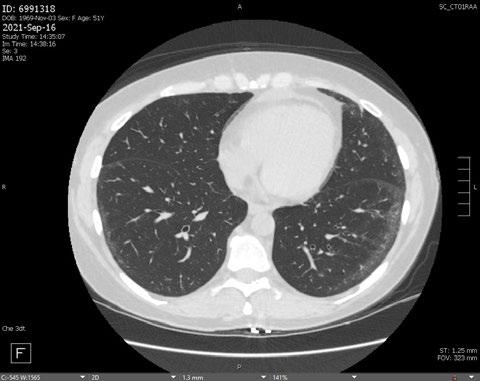

Radiogenomics Relationship of Nonsmall Cell Lung Cancer: Preliminary Results

Citation: EMJ Radiol. 2024;5[1]:24-25. https://doi.org/10.33590/emjradiol/10304578.

BACKGROUND AND AIMS

Radiomics, an emerging paradigm in medical imaging, entails the quantitative analysis of tumour features, and has exhibited potential in predicting treatment responses and outcomes. Furthermore, within the domain of -omics assessments, the significance of comprehensive genetic evaluation in non-small cell lung cancer (NSCLC) is on the rise, influenced by both biological and therapeutic considerations.

The aim of this study was to correlate radiomics features with the genetic results obtained from liquid biopsy in patients with lung tumours. The prediction of tumour genetics in radiomics relies on the presumption of conducting a non-invasive evaluation of molecular characteristics in tumour tissues, which can be challenging in certain tumour types, such as NSCLC. Therefore, in this context, the authors considered it pertinent to explore and generate hypotheses regarding the technical feasibility of identifying associations between genomics acquired through liquid biopsy assessments and radiomics.

MATERIALS AND METHODS

This observational, prospective study integrated radiomic perspectives using CT and genomic perspectives, through next-generation sequencing applied to liquid biopsies.

The authors included 62 patients with NSCLC who underwent pre-surgery CT (Revolution™ 128 MDCT, GE HealthCare, Chicago, Illinois, USA) at the Radiology Department of Campania University Luigi Vanvitelli, Naples, Italy. Every patient for whom liquid biopsy was performed gave informed consent for the genetic analysis. For the radiomic analysis, image processing CT volumes were manually delineated using ITK-SNAP 3.8.0 (University of Pennsylvania, Philadelphia, USA). Radiomics features (first order: Gray Level Co-occurrence Matrix, Gray Level Run Length Matrix, Gray Level Size Zone, Gray Level Dependence Matrix, and Neighbouring Gray Tone Difference Matrix) were computed using Pyradiomics1 in Python 3.7 (Python Software Foundation, USA) environment.

Radiomic features were derived from CT images, and genetic assessments were performed using a comprehensive panel targeting 523 cancerrelated genes. For the statistical analysis, association between radiomic features and gene mutations were assessed using feature importance based on receiver operating characteristic curve analysis; moreover, a machine learning approach based on support vector machine was used to evaluate the ability of radiomic features to predict gene mutations.

Associations between radiomic features and genetic mutations were established using the area under the receiver operating characteristic curve. Machine learning techniques, including support vector machine classification, aimed to predict genetic mutations based on radiomic features. The prognostic impact of selected gene variants was assessed using Kaplan–Meier curves and log-rank tests.

RESULTS

Sixty-two patients underwent screening, with 53 being comprehensively characterised radiomically and genomically. This group was predominantly male (68.4%), and adenocarcinoma was the prevalent histological type (73.7%). Most patients exhibited ECOG Performance Status of 0 or 1 (87.7%), and 91.2% had a history of former or current smoking. Disease staging was distributed across I–II (38.6%), III (31.6%), and IV (29.8%). Significant correlations were identified with mutations

Abstract ● ECR 2024 24 Radiology ● April 2024 ● Creative Commons Attribution-Non Commercial 4.0

of ROS1 p.Thr145Pro (shape_Sphericity), ROS1 p.Arg167Gln (glszm_ZoneEntropy, firstorder_TotalEnergy), ROS1 p.Asp2213Asn (glszm_GrayLevelVariance, firstorder_ RootMeanSquared), and ALK p.Asp1529Glu (glcm_Imc1). Patients with the ROS1 p.Thr145Pro variant demonstrated markedly shorter median survival compared to the wild-type group (9.7 months versus not reached; p=0.0143; hazard ratio: 5.35; 95% confidence interval: 1.39–20.48).

CONCLUSION

This study contributes to advancing the prediction of cancer genetics through the application of non-invasive radiomic techniques. The prediction of tumour genetics in radiomics hinges on the assumption of conducting a non-invasive assessment of molecular characteristics in tumour tissues, which can pose challenges in certain tumour types, such as NSCLC. Therefore, within this context, the authors deemed it relevant to explore and formulate hypotheses regarding the technical feasibility of identifying associations between genomics obtained through liquid biopsy assessments and radiomics.

Specific radiomic features illustrate the capability to predict non-synonymous mutations of ROS1 and ALK in patients with NSCLC. Investigating the prediction of cancer genetics using non-invasive radiomic techniques represents an innovative frontier in scientific research, which is currently undergoing extensive investigation. Research on the use of conventional CT features and CT image-based radiomic features to predict the gene mutation status of lung cancer is still in its nascent stages.

The integration of radiomic techniques in predicting cancer genetics holds potential, but is constrained by cost and technological limitations. Despite these challenges, the authors’ study explores the relationships between genomics and radiomics, revealing specific genetic variants associated with radiomic features. While acknowledging limitations, particularly the small sample size and the lack of actionable mutations, this research lays the groundwork for broader investigations aiming to link radiomics and genomics in NSCLC. The ultimate objective is to improve prognostic accuracy and refine therapeutic strategies. ●